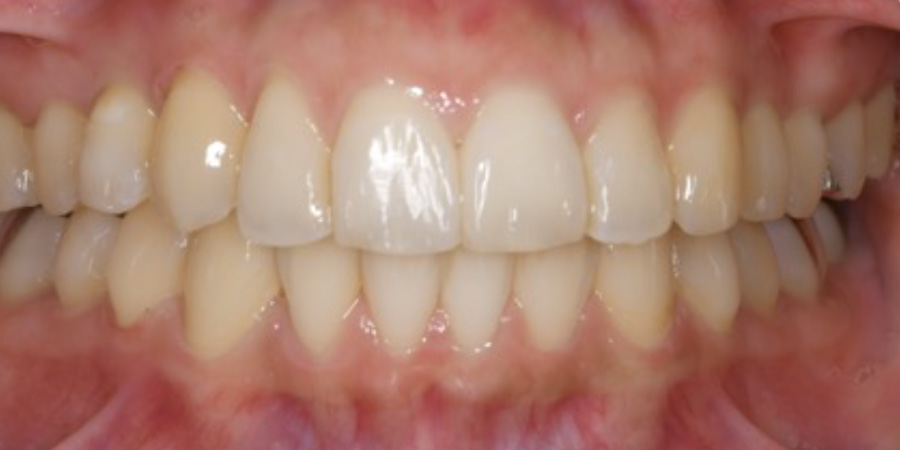

歯並びを治したい

【マウスピース矯正】

- 歯並びを治したい

- 2年6か月

- マウスピース矯正

935,000円(税込)

- 目立ちにくいマウスピース矯正(非抜歯矯正)

歯と歯の間に隙間をつくることにより、歯列弓を広げながら治療を行いました。

- ・後戻りする可能性があるのでリテーナーを最低でも矯正期間以上はつけること

・稀にほっぺた、唇、舌などに口内炎や傷ができることがあります